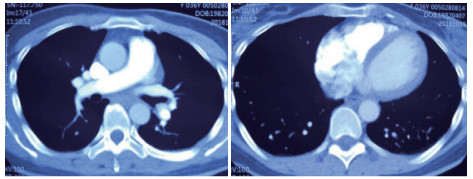

例2 72岁,男性。主因“活动后气短3 d,加重伴有晕厥1次”住院。既往体健,否认制动史及手术史。入院查体:神志清楚,体温36℃,血压120/70 mmHg,脉搏110次/min,呼吸22次/min,脉氧93%(安静,空气氧),轻度乏氧征。双肺呼吸音清,未闻及干湿性啰音。心率110次/min,心律齐,P2 > A2,心界无扩大,无杂音。腹软,无压痛,肠鸣音正常,双下肢无浮肿。神经系统查体未见异常。血气分析(安静,空气氧)提示pH 7.457,PaCO2 26.7 mmHg,PaO2 74.0 mmHg,SaO2 95.5%;D-Dimer 13 743 ng/ml;FDP 175.060 μg/mL,FBG 1.990 g/L;PLT:224 G/L;cTnI 0.04 ng/mL,BNP 666 pg /mL;ALT 15 U/L,AST 27 U/L,CREA 103.3 mmol/L,血Na+、K+、Cl-:正常范围;UCG提示:右心增大,肺动脉主干增宽(28 mm),三尖瓣反流(中-重度),反流面积11.5 cm2,TI法估计SPAP为50 mmHg、左室舒末内径38 mm、左心功能稍减低E波/A波= 60/40 cm/s,未见节段性室壁运动障碍;双下肢静脉超声提示右侧股总、股深、股浅、腘静脉及双侧小腿肌间静脉丛血栓形成。心电图(图 5所示)提示窦性心动过速;CTPA提示双肺主干明确充盈缺损(图 6所示)。入院诊断:急性PE(中高危)。给予低分子肝素重叠华法令抗凝治疗。D-Dimer由入院时13 743 ng/mL分别降至第2天10 000 ng/mL,第3天9 000 ng/mL和第四天的5 000 ng/mL。住院第4天开始出现纳差、恶心未吐,复查心电图提示窦性心动过速,SⅠQⅢTⅢ,胸导T波加深(如图 7所示)。入院第5天床上排便后出现呼吸急促,储氧面罩吸氧(Flow 10 L/min)维持氧合78%(当天INR 2.02),15 min后出现血压、心率下降至消失,心外按压始终无自主呼吸及心律恢复,因家属放弃系统溶栓治疗,抢救2 h无效宣告患者临床死亡。回顾入院后连续复查的心电图提示右心负荷有逐渐加重及胸前导联缺血加重的倾向;UCG同样证实右心室内径呈进行性增大的趋势(分别为入院时的右心房31 mm×47 mm、第2天28 mm×40 mm和第4天的54 mm×60 mm)。

| 图 6 入院时CTPA提示双肺主干明确充盈缺损 |

2 积极寻找补救性溶栓的治疗时机并非遥不可及例3 36岁,女性。主诉“活动后气短5 d、加重伴咯血1 d”。既往因月经不调,应用激素替代治疗20 d;否认手术、外伤及制动史。入院查体:神志清楚,体温36.8℃,血压110/75 mmHg,脉率118次/min,呼吸23次/min,脉氧饱和度90%(安静,空气氧),轻度乏氧征。双肺呼吸音清。心率118次/min,未闻及干、湿性啰音,心律齐,P2 > A2,心界无扩大,无杂音,腹软,无压痛,肠鸣音正常,双下肢无浮肿。神经系统查体未见异常。血气分析(空气氧)提示pH 7.415,PaCO2 38.3 mmHg,PaO2 89.90 mmHg,SaO2 89.90%;D-Dimer 1 684 ng/mL;FDP 8.670 μg/mL,FBG 3.510 g/L;PLT 151.0 G/L;cTnI 0.00 ng/mL,BNP 58.00 ng/mL;ALT 27 U/L,AST 17 U/L,CREA 53.7 μmol/L,血Na+、K+、Cl-大致正常;UCG提示:右室壁运动减低,左室壁运动不协调,各室壁厚度正常,三尖瓣环位移14 mm,右室面积变化率19%,各瓣膜形态及运动未见异常,收缩期三尖瓣房侧见少量反流信号,T1法估测SPAP:24 mmHg;双下肢静脉超声提示:右下肢深静脉血栓形成。心电图(图 8所示)提示窦性心动过速;CTPA提示双肺主干明确充盈缺损(图 9所示)。入院诊断:急性PE(中低危)。给予低分子肝素抗凝治疗。入院24 h内,大便时出现胸闷、心悸主诉,SpO2由93%(不吸氧)降至88%(储氧面罩吸氧,Flow 10 L/min);D-Dimer由入院时1 026 ng/mL升至4 100 ng/mL,血压110/70 mmHg。因血氧有恶化趋势遂决定给予静脉溶栓治疗(r-tPA 50 mg,2 h内泵入),溶栓治疗结束后2 h复查凝血提示D-Dimer 45 000 ng/mL。溶栓2 h患者症状明显好转;心电图提示窦性心动过速,SⅠQⅢTⅢ征象较前改善,胸前导联出现冠状T波(图 10所示)。溶栓后24 h复查CTPA右肺主干血栓明显消失,右心室较前明显缩小(图 11所示)。

| 图 9 入院时CTPA提示右肺动脉主干充盈缺损、左肺亚段水平充盈缺损、右心室增长 |